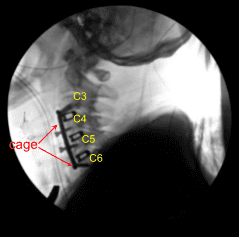

Bilateral foraminotomies were done using Kerrison punch 3.0. All the discs were thoroughly decorticated to achieve fusion. Once adequate foraminotomy and discectomy was done, a spacer was inserted to size the disc. After sizing, 8-mm Globus titanium cage filled with titanium interbody spacer, filled with autologous bone graft, mixed with Trinity and DBX was inserted finding it in adequate position.

Attention was moved to the C4-5 disc space. Caspar pin was inserted into the C5 body and expansion of C4-5 done with a self-retaining retractor. Skyline was moved inferiorly to retract medially and laterally. Discectomy was done in a similar fashion followed by excision of the posterior longitudinal ligament and bilateral foraminotomies. After adequate excision the sizing was done, Globus titanium spacer filled with Trinity and autologous bone graft and DBX was inserted again.

Again, a new pin was inserted into the C6 body and similar discectomy was done using curettes,matchstick bur and Kerrison punches. PLL was also excised. Bilateral foraminotomies of C5-6 was performed. A matchstick bur was used each time to make holes into the end plates for better fusion.

The cage was inserted, again packed with autologous bone graft, Trinity and DBX. After inserting all the three cages, the bony contouring was done using matchstick bur and plate was put of an adequate size. The plate was found to be adequate in AP and lateral views in a satisfactory position.

The plate was fixed using locking variable angle screws in the body of C3, C4, C5, and C6. Final pictures were taken and saved. The wound was thoroughly washed and hemostasis was achieved. The retractors were removed. Closure was done in layers using #2-0 Vicryl and Monocryl. Dressing was applied.